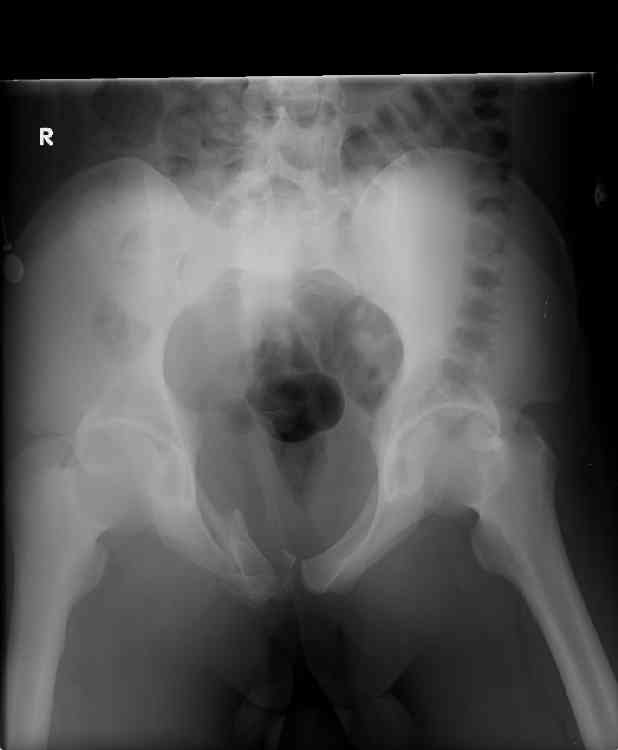

hello,this is a healthy 22yo male. peds vs auto.

no other injuries. has anyone treated these non-operatively? thanks.

It's type A pelvic-ring lesions. Because

the pelvic ring is stable, it

cannot be displaced by physiologic

forces and may be treated non-operativly in male.

One bit of important yet omitted info is the patient's physical exam... if this pelvic ring injury is unstable to exam, then I'd recommend operative reduction and stable fixation to him.